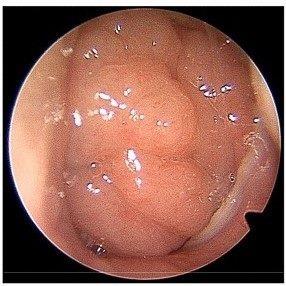

發稿日期:115年2月5日 小孩也會得慢性鼻竇炎 症狀與治療與成人大不同 慢性鼻竇炎並非成人專屬疾病,兒童同樣可能罹患,但在症狀表現、診斷方式與治療策略上,與成人慢性鼻竇炎存在明顯差異。臺北市立聯合醫院陽明院區耳鼻喉科主任陳冠瑋提醒,若未及早正確診斷與治療,可能影響孩童生活品質與學習表現,家長不可輕忽。 成人與兒童症狀不同 咳嗽是小兒重要警訊 陳冠瑋指出,成人慢性鼻竇炎最常見的四大症狀包括:膿鼻涕、鼻塞、顏面疼痛或壓迫感,以及嗅覺減退;而小兒慢性鼻竇炎的四大症狀則為:膿鼻涕、鼻塞、顏面疼痛或壓迫感與咳嗽。 在臨床上,小兒最常見的症狀其實是長期流鼻涕或鼻水,其次則是咳嗽,而且多半為有痰的咳嗽,夜間或躺下時症狀會更加明顯,常被誤認為單純感冒或過敏。 此外,鼻息肉在小兒慢性鼻竇炎中相對少見,若發現孩童合併鼻息肉,醫師會進一步評估是否存在其他罕見疾病。 氣喘與慢性鼻竇炎高度相關 需整體評估 研究顯示,約有20%的慢性鼻竇炎患者同時合併氣喘;反過來看,約有60%至70%的氣喘患者可發現鼻竇黏膜增厚的情形,且氣喘越嚴重,合併慢性鼻竇炎的比例越高。 陳冠瑋補充,特別是合併鼻息肉的慢性鼻竇炎,與氣喘的關聯性更為密切,因此在治療上,常需耳鼻喉科與胸腔科或小兒科共同評估,才能達到較好的控制效果。 小兒慢性鼻竇炎以保守治療為主 避免濫用抗生素 在治療方面,小兒慢性鼻竇炎的初步治療以鼻腔沖洗(洗鼻子)及類固醇鼻噴劑為主,有助於減少發炎與分泌物堆積。 若出現急性惡化時,醫師可依病情短期使用抗生素或口服類固醇,但不建議長期使用抗生素作為慢性治療。至於目前成人常使用的生物製劑(單株抗體),在小兒慢性鼻竇炎的應用仍缺乏足夠研究證據,尚未成為常規治療選項。 腺樣體肥大是關鍵因素 必要時考慮手術 腺樣體肥大在小兒慢性鼻竇炎中扮演重要角色。若藥物治療效果不佳,且檢查發現腺樣體明顯肥大,手術治療通常會優先考慮腺樣體切除術,再依病情評估是否需要進一步接受內視鏡鼻竇手術。 小兒內視鏡鼻竇手術已被證實是安全的,且多數可改善術後症狀;另外,鼻竇氣球擴張術也是治療選項之一,但目前在小兒族群中的角色仍需更多研究佐證。 醫師提醒:孩子久咳、流鼻涕別輕忽 陳冠瑋提醒,若孩童出現長期流鼻涕、夜間咳嗽、有痰咳嗽或鼻塞反覆不癒,不應僅當作感冒處理,建議及早至耳鼻喉科檢查。透過正確診斷與個別化治療,多數小兒慢性鼻竇炎都能獲得良好控制,讓孩子恢復正常呼吸與生活品質。